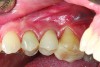

The implant of the patient shown in Figure 8 demonstrated all three of the red flag situations: it was placed too far buccally, had inadequate bone and soft tissue at the time of implant placement, and lost bone and soft tissue post implant placement. Correcting this required increased time, cost, and surgeries (Figure 9).

A implant restoration with a buccal dehiscence of bone and soft tissue caused by poor implant positioning, lack of keratinized tissue prior to implant placement, and soft tissue recession post implant restoration.

Figure 8

The same implant in Fig 8, 7 years following treatment, which included two autogenous connective tissue grafts and a bone augmentation surgery with a combined allograft and xenograft mixed with two biologics.

Figure 9